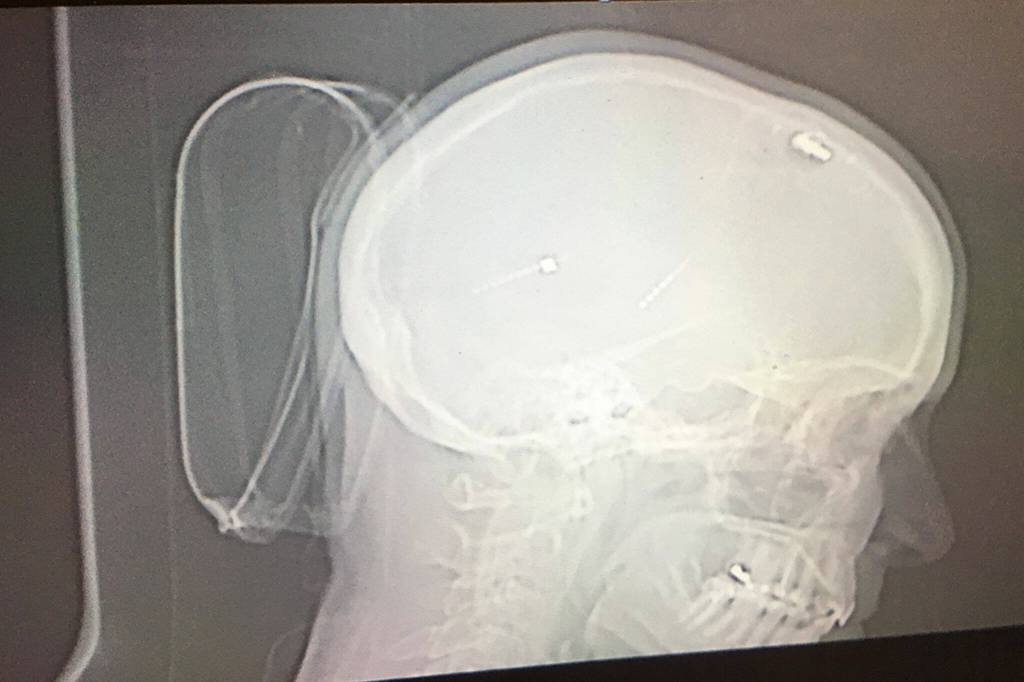

Two years ago, Osborne was able to make the shaking in her right hand stop with help from Swedish’s doctors in Seattle and Deep Brain Stimulation (DBS). As she describes it, Osborne said a neurostimulator was installed in her skull with a wire to a generator/battery about the size her palm placed inside her chest just below her left collarbone telling her hand not to shake (through low-intensity electrical impulses to nerve structures).

For Osborne, DBS was installed on the left side of her brain and chest to help her right side’s tremors.